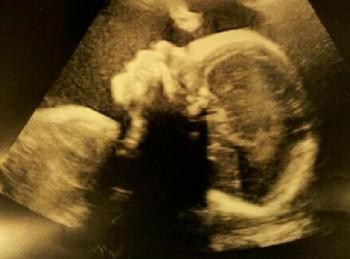

så fik jeg min vækstscanning overstået idag

og sikke hun hygger sig derinde

og WOW hun er da godt nok vokset på de 3½ uge det er siden jeg sidst fik hende skønnet....

dengang vejede hun 700g..... idag.... ta daaaaaa... 1313g

så hun ligger stadig i toppen af normalen

så fortsætter hun sådan skyder de hende til at blive et barn lige under de 4 kg

i skal ikke snydes af lidt billeder af lillepigen som denne gang var lidt mere villig til at vise sit ansigt